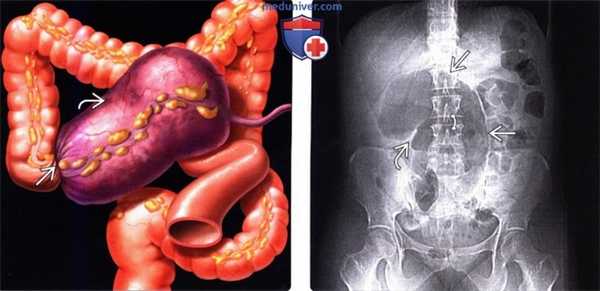

(Слева) На рисунке показано скручивание (заворот) В восходящей ободочной кишки, что привело к обструкции просвета и нарушению кровообращения. Слепая кишка В расширена и вместе с брыжейкой смещена влево и кверху.

(Справа) На рентгенограмме в положении пациента лежа на спине визуализируется растянутая газом слепая кишка, находящаяся по центру живота. Основание слепой кишки направлено кверху, а илеоцекальный клапан направлен в латеральную сторону. Тонкая кишка растянута с наличием газа, в то время как левая половина ободочной кишки находится в относительно спавшемся состоянии.

(Справа) На рентгенограмме в положении пациента лежа на спине визуализируется растянутая газом слепая кишка, находящаяся по центру живота. Основание слепой кишки направлено кверху, а илеоцекальный клапан направлен в латеральную сторону. Тонкая кишка растянута с наличием газа, в то время как левая половина ободочной кишки находится в относительно спавшемся состоянии. (Слева) На аксиальной КТ у этого же пациента определяется выраженное растяжение слепой кишки и симптом «водоворота» со стороны илеоцекальной брыжейки в нижних отделах живота справа.